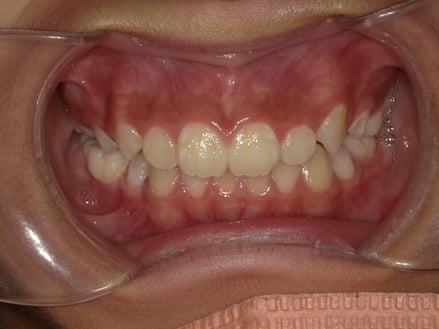

この子の歯をよ~く見てみてください。

↓↓

所々はっきりと濁りが見えるのがわかりますか?

歯垢やプラークと呼ばれるヌルヌルとした汚れがたくさん付いていますね。